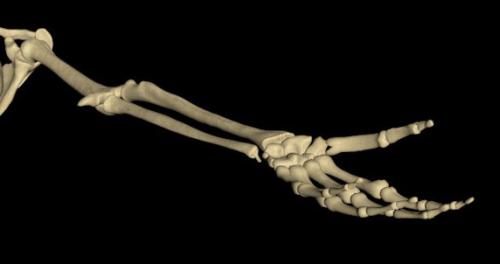

Лучезапястный сустав (articulatio radiocarpea)

сочленение дистального конца лучевой кости предплечья с проксимальным рядом костей запястья. Функционально является частью сложного кистевого сустава, в который входят кроме лучезапястного сустава среднезапястный, межзапястный, запястно-пястный, межпястный и дистальный лучелоктевой суставы. Эти суставы находятся в тесном анатомическом и функциональном единстве ( рис. 1—4 ).

Суставную ямку Л.с. образует запястная суставная поверхность лучевой кости, дополненная с локтевой стороны суставным диском треугольной формы, отделяющим полость Л.с. от полости дистального лучелоктевого сустава. Суставную головку составляет проксимальный ряд костей запястья: ладьевидная, полулунная и трехгранная кости, соединенные между собой межкостными межзапястными связками. Широкая и тонкая суставная капсула укреплена на тыльной поверхности тыльной лучезапястной связкой, на ладонной — ладонной локтезапястной и ладонной лучезапястной связками, а на боковых — локтевой и лучевой коллатеральными связками запястья.

Лучезапястный сустав относится к двуосным суставам с эллипсоидной формой суставных поверхностей, что позволяет выполнять сгибание, разгибание, приведение (локтевое сгибание), отведение (лучевое сгибание) и круговые движения кисти. Основными мышцами, сгибающими кисть, являются лучевой и локтевой сгибатели запястья, а также длинная ладонная мышца. Разгибание производят длинный и короткий лучевые и локтевой разгибатели запястья. Остальные мышцы, расположенные на предплечье, принимают косвенное участие в движениях кисти. Отведение обеспечивают короткий и длинный лучевые разгибатели запястья, лучевой сгибатель запястья, длинная мышца, отводящая большой палец, а также длинный и короткий разгибатели большого пальца. Приведение осуществляется благодаря одновременному действию локтевых сгибателя и разгибателя запястья. В области Л.с. расположен треугольной формы промежуток, так называемая анатомическая табакерка, который ограничен спереди и снаружи сухожилиями короткого разгибателя большого пальца и длинной, отводящей большой палец мышцы, а сзади — сухожилием длинного разгибателя большого пальца. Дном анатомической табакерки являются ладьевидная и трапециевидная кости, вершиной — основание первой плюсневой кости, основанием — наружный край лучевой кости. В описанном промежутке проходят лучевая артерия и поверхностная ветвь лучевого нерва.